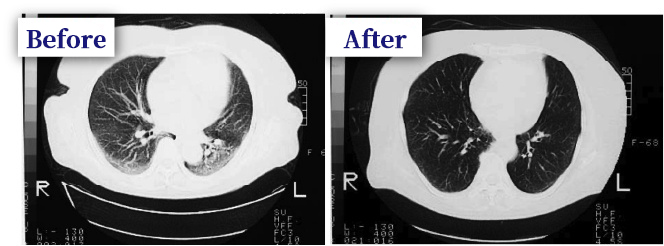

Example of treatment 70 years old male, Mr. C

Suspected of having latent pulmonary thrombotic symptoms, he was admitted to another hospital as pneumonia. After 2 months of treatment,

After 2 months of treatment, CT scan of the left side of the chest showed that there was still a shadow in the posterior and right middle lung lobe, and that she had difficulty breathing even after walking about 80 meters.

He had difficulty breathing after walking about 80 meters and had severe dynamic symptoms.

After treatment with intravenous infusion, most of the shadows disappeared as shown in the center of the picture, and in the right picture, most of the shadows disappeared,

The symptoms of dyspnea also improved. She no longer had difficulty breathing even after walking two kilometers to and from the hospital, and she no longer had severe dynamic symptoms.